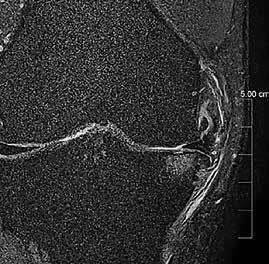

Klinische Vorteile von AiCE in der Routine Da AiCE das Rauschen vermindert, haben wir bei der Aufnahme die Möglichkeit, das Signal des MR-Bildes zu verkleinern, ohne das Gleichgewicht von Signal zu Rauschen ungünstig zu beeinflussen. Dieser Effekt kann entweder dazu genutzt werden, um Bilder schneller aufzunehmen und somit die Untersuchungszeit zu verkürzen oder um Bilder mit kleineren Voxeln aufzunehmen und somit die Auflösung zu verbessern. Beide Effekte können erreicht werden, weil durch AiCE das Signal-Rausch-Verhältnis verbessert wird.

Ziel der Forschungen an der Universität Bordeaux war die hochaufgelöste und detailreiche Darstellung spezieller Hirnareale, wie des Hippocampus oder des Claustrum. Diese Regionen hatte Prof. Tourdias schon am 7T-System bei seinem Aufenthalt an der Stanford-Universität studiert. Nun war es mit der AiCE-Technologie möglich, vergleichbar aufgelöste Bilder auch bei 3T in akzeptabler Untersuchungszeit zu erzeugen (siehe Abb. 5 a und b).

Natürlich lassen sich die Vorteile einer höheren Auflösung nicht nur in der klinischen Forschung nutzen, sondern sind auch dazu geeignet, bei-

Abb. 5 a + b: Hochaufgelöstes Bild des Hippocampus; 0,15 mm x 0,15 mm; 2 mm Schichtdicke; rechts mit AiCE-Rekonstruktion. Mit freundlicher Genehmigung des Unversitätsklinikums Bordeaux. Abb. 6 a + b: Hochaufgelöstes Bild des Knies; 0,15 mm x 0,15 mm (interpoliert); 1 mm Schichtdicke; rechts mit AiCE-Rekonstruktion.

42 // VISIONS 31

spielsweise einen Knorpelschaden im Knie im Detail zu zeigen.

Durch die alternative Nutzung des SNR-Gewinns durch AiCE werden MR-Untersuchungen ohne Auflösungsverlust beschleunigt. Der große klinischen Vorteil bei diesem Einsatz von AiCE ist, dass es bei Patienten zu weniger Artefakten durch Bewegung kommt. Die Quote von Wiederholungsaufnahmen wird deutlich reduziert bei gleichzeitiger Steigerung des Bildqualität. Vereinfacht gesagt steigt die Untersuchungskapazität des MRTs. Zur Beschleunigung der Untersuchungsdauer eignet sich besonders das neue Compressed-SPEEDER-Verfahren, das völlig unabhängig von Spulentyp und Untersuchungsrichtung zum Einsatz kommt.

A T1-Gewichtung; Auflösung 0,35 mm x 0,35 mm; 59 Sek.

B T2-Gewichtung; Auflösung 0,3 mm x 0,3mm; 57 Sek.